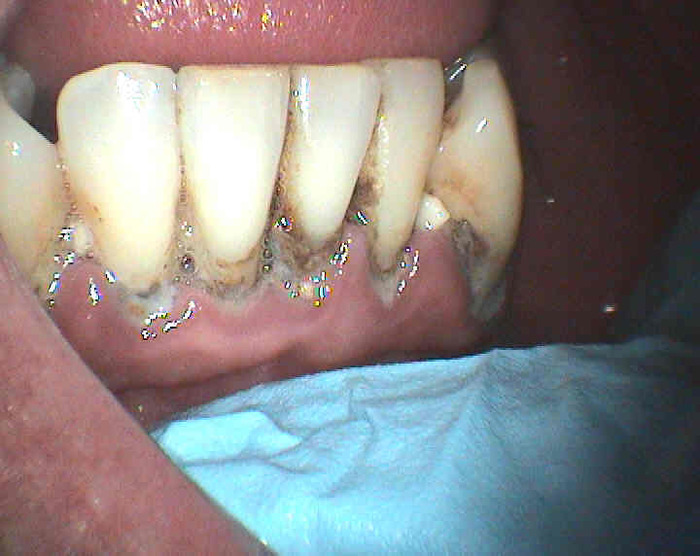

Úvod > Informace > Zubní kámen > Zubní kámen